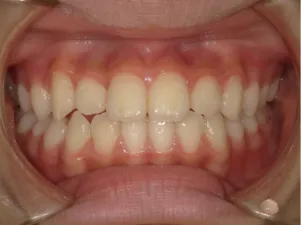

治療後⑩高2:17y7m 抜歯治療終了

口元の治療前後:15y5m→17y7m スッキリしました